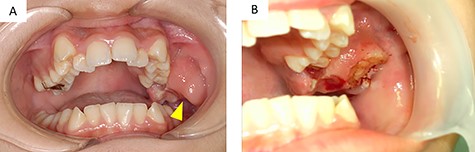

A 12-year-old girl presented to our clinic with a chief complaint of trismus. A few months ago, she noticed a bulge in the left maxillary gingiva and trismus. There was no spontaneous pain, but pressure pain was felt. She was afebrile, had no history of trauma or medications. During her first medical examination at our clinic, she was 164 cm tall, weighed 54 kg. Extraoral examination revealed a slight bulge in the left cheek with countenance, right and left asymmetry and trismus. The range of mouth opening was 18 mm, and there were no swollen lymph nodes that I could feel in the neck. Intraoral findings revealed a neoplastic lesion extending from the left maxillary first molar to the maxillary tuberosity (Fig. 1A). It interfered with the occlusion on that side.

(A) intraoral findings of a suspected neoplastic lesion extending from the maxillary tuberosity to the left maxillary first molar at the time of initial examination (arrowhead); (B) intraoral findings at the time of biopsy; the sectioned surface was milky-white with enhancement characteristics

Three days after the first medical examination, a biopsy of the lesion was performed in the left maxillary gingiva with the consent of the patient and parents to obtain a definitive diagnosis. The sectioned surface was milky-white with enhancing characteristics (Fig. 1B). Histopathological examination showed proliferation of oval to spindle-shaped cells, with hyperchromatic nuclei and a high nuclear-cytoplasmic ratio, arranged in a fascicular pattern (Fig. 3A). Mitotic figures were frequently observed. Focally, the tumor cells were arranged in small nests and in a pseudo-capillary pattern in the sclerotic collagenous stroma (Fig. 3B). Immunohistochemical examination revealed that the tumor cells were positive for desmin, myoD1, myogenin, mammary serum antigen and glial fibrillary acidic protein (Fig. 4A–C). The Ki67 proliferation index was ~30% per HPF (Fig. 4D). The details of immunostaining are shown in Table 1. The patient was diagnosed with RMS classified as Group III according to the Intergroup Rhabdomyosarcoma Study (IRS) grouping system [4]. The left maxillary gingiva RMS was treated via proton beam irradiation at 59.4 Gy and with vacuum-assisted wound closure therapy with 14 cycles of vincristine, actinomycin D and cyclophosphamide. After chemoradiotherapy, a complete response was documented via image evaluation.